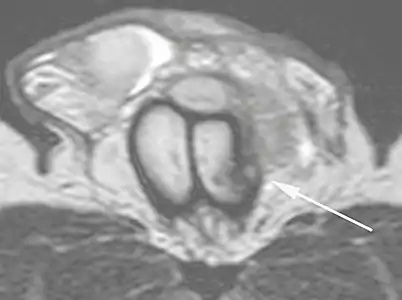

Ultrasound examination is able to depict the tunica albuginea tear in the majority of cases (as a hypoechoic discontinuity in the normally echogenic tunica). In a study on 25 patients, Zare Mehrjardi et al. concluded that ultrasound is unable to find the tear just when it is located at the penile base. In their study magnetic resonance imaging (MRI) accurately diagnosed all of the tears (as a discontinuity in the normally low signal tunica on both T1- and T2-weighted sequences). They concluded that ultrasound should be considered as the initial imaging method, and MRI can be helpful in cases that ultrasound does not depict any tear but clinical suspicions for fracture are still high. In the same study, authors investigated accuracy of ultrasound and MRI for determining the tear location (mapping of fracture) in order to perform a tailored surgical repair. MRI was more accurate than ultrasound for this purpose, but ultrasound mapping was well correlated with surgical results in cases where the tear was clearly visualized on ultrasound exam.[10] The advantage of ultrasound in the diagnosis of penile fracture is unrivaled when its noninvasive, cost-effective, and nonionising nature are considered.[11]

Figure 4 A: Ultrasound of the penis, right lateral view. Longitudinal section showing rupture of the tunica albuginea with an adjacent 1.92 cm hematoma (between calipers), due to trauma.[2] B: Axial T2-weighted turbo spin-echo magnetic resonance imaging scan showing left-sided discontinuity of the tunica albuginea (arrow), secondary to fracture.[2]

B: Axial T2-weighted turbo spin-echo magnetic resonance imaging scan showing left-sided discontinuity of the tunica albuginea (arrow), secondary to fracture.[2]